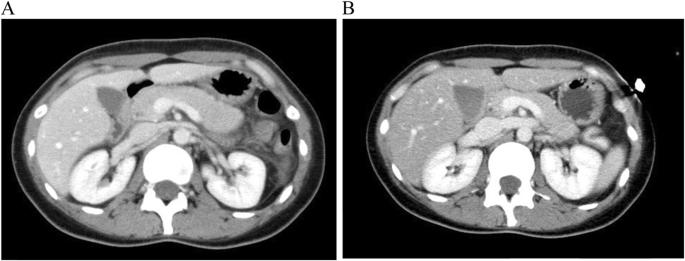

A 31-year-old Japanese woman who presented with upper abdominal pain was admitted to a local hospital. She had a history of mycoplasma pneumonia in childhood and a family history of diabetes mellitus of her father. Four days before admission, she had a fever over 37 degrees and received an antipyretic agent at the local clinic, while flu testing results were negative. On admission to the local hospital, serum amylase was elevated to 370 IU/L, and abdominal computed tomography (CT) scanning showed pancreatic swelling and mild ascites (Fig. 1a). She was diagnosed with acute pancreatitis (grade 1) and treated with ulinastatin. The morning after admission, her fasting serum glucose, insulin and C-peptide level were within normal ranges: 101 mg/dL, 2.2 μIU/L and 0.8 ng/mL, respectively. At 4 days after admission, she complained of nausea and low back pain, and fell to consciousness disturbance (Japan Coma Scale II-10: drowsiness) with hyperglycemia (861 mg/dL) and metabolic acidosis. She was diagnosed with diabetic ketoacidosis and transferred to our hospital.

Although serum amylase (1800 U/L, Fig. 2), lipase and trypsin (320 U/L and 3040 ng/mL respectively) were elevated, reexamination with CT scanning (Fig. 1b) showed amelioration of the pancreatic swelling and magnetic resonance cholangiopancreatography (MRCP) imaging depicted no abnormalities, even in the pancreas (data not shown). On the second day in our hospital, her symptoms showed improvement, and the serum glucose level had fallen below 200 mg/dL. However, on the 3rd hospital day, electrocardiography (ECG) depicted ST-segment elevation in V3-V6 (Fig. 3) without typical cardiac symptoms but serum creatinine kinase (CK) (830 U/L, Fig. 2), CK-MB and troponin I (49 U/L and 11.99 ng/mL respectively) were elevated. Coronary angiography showed no abnormal findings. Left ventriculography (LVG) showed apical wall hypokinesis, while no other abnormal findings, including takotsubo cardiomyopathy, were detected. On the 4th hospital day, abnormal ECG findings showed improvement and serum myocardial necrosis markers had normalized. On the 8th hospital day, contrast-enhanced cardiac magnetic resonance imaging (MRI) indicated late gadolinium enhancement (LGE) in the apical wall (Fig. 4). She was diagnosed with acute myocarditis based on the guidelines for diagnosis of myocarditis [9]. It should be noted that no abnormality was observed in echocardiogram examination and that serum CK level was 156 U/L at the previous hospital. On the 28th hospital day, follow-up cardiac MRI showed no LGE in the apical wall.